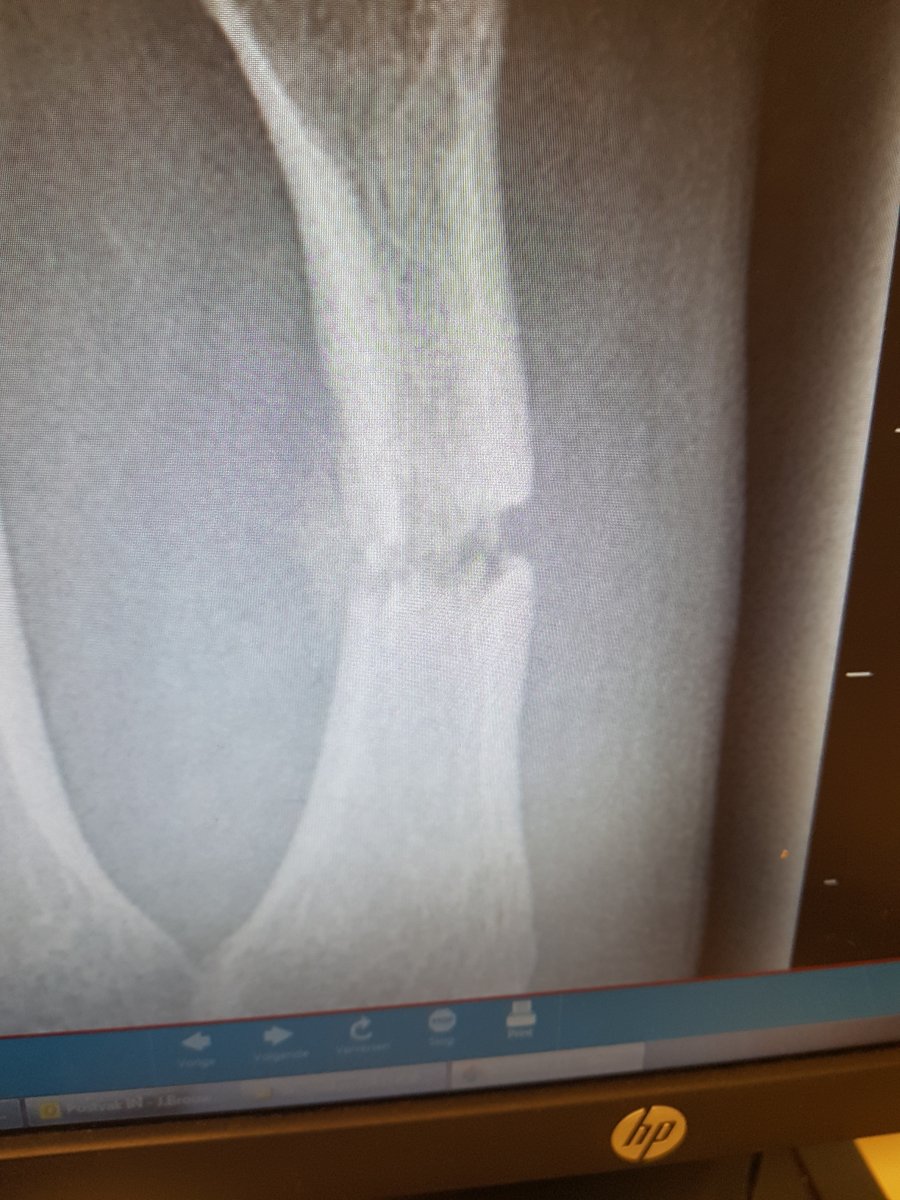

als er over 3 weken geen verbetering is moet er misschien alsnog een operatie plaatsvinden.. WTF is dat

??